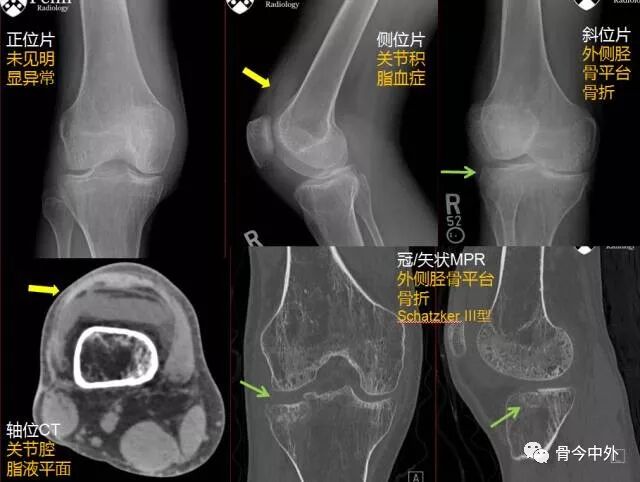

雙語病例 脛骨平台骨折引發的思考 骨今中外 微文庫

病例讨论 应用mipo技术治疗schatzker 型胫骨平台骨折 骨今中外 微信公众号文章阅读 Wemp

胫骨平台骨折schatzker 分型总结 影像ppt